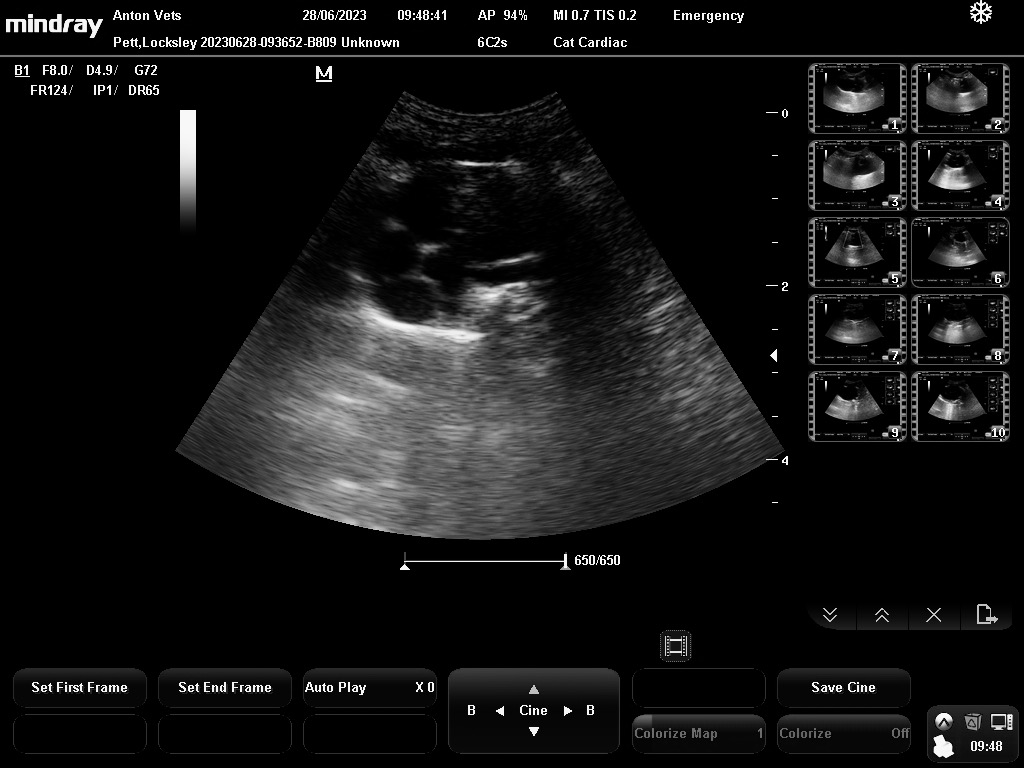

But back to us guinea pigs. We’re all fine, really I’m officially fine, because if you remember, I went to see Dr Rebekah to have my insides scanned. It was particularly to check my heart. Dr R showed Mummy the pictures and also a moving picture which showed my heart pumping away regular as clockwork. I haven’t got that, but here’s the picture of my heart:

The heart is in the top section, and the black is my blood, and the white marks in there are the heart valves, working away. And below, the greyish stuff is my body and chest, and it shows there’s no congestion or breathing problems.